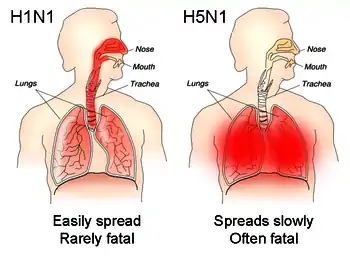

For instance, part of the process that allows influenza viruses to invade cells is the cleavage of the viral hemagglutinin protein by any one of several human proteases.[71] In mild and avirulent viruses, the structure of the hemagglutinin means that it can only be cleaved by proteases found in the throat and lungs, so these viruses cannot infect other tissues. However, in highly virulent strains, such as H5N1, the hemagglutinin can be cleaved by a wide variety of proteases, allowing the virus to spread throughout the body.[94]

The viral hemagglutinin protein is responsible for determining both which species a strain can infect and where in the human respiratory tract a strain of influenza will bind.[96] Strains that are easily transmitted between people have hemagglutinin proteins that bind to receptors in the upper part of the respiratory tract, such as in the nose, throat and mouth. In contrast, the highly lethal H5N1 strain binds to receptors that are mostly found deep in the lungs.[97] This difference in the site of infection may be part of the reason why the H5N1 strain causes severe viral pneumonia in the lungs, but is not easily transmitted by people coughing and sneezing.[98][99]